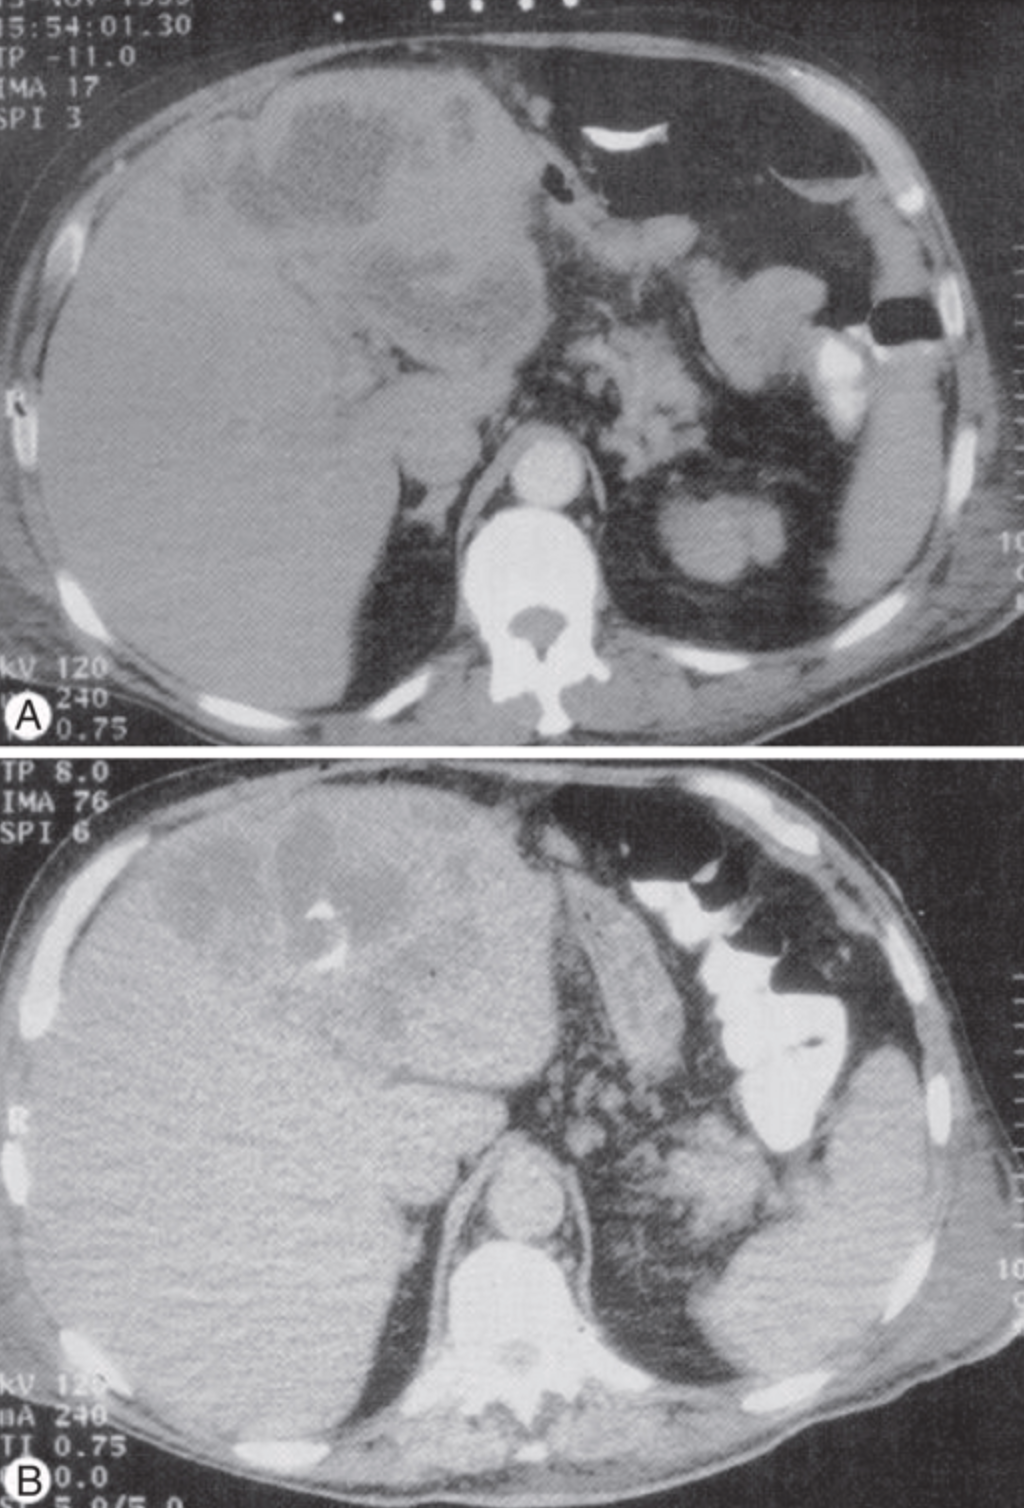

Figure 11: CT imaging of pyogenic liver abscess with percutaneous drainage. CT-guided aspiration is the preferred approach for both diagnostic confirmation and therapeutic drainage.

Figure 12: CT-guided drainage of liver abscesses. (A) CT revealing multiple hypodense lesions in the right hepatic lobe; (B) follow-up showing catheter in place and decrease in abscess size.